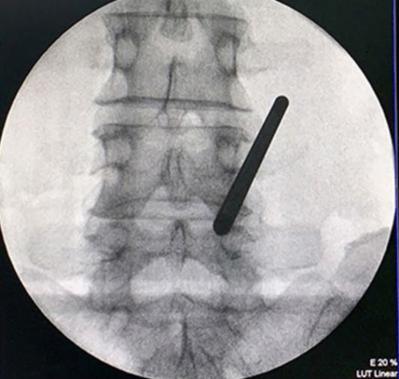

• 不同入路脊柱内镜手术治疗L4/5节段脱垂型腰椎间盘突出症的疗效比较

摘要:目的 观察经椎间孔入路内镜下腰椎间盘切除术(TELD)和经椎板间入路内镜下腰椎间盘摘除术(IELD)治疗L4/5节段脱垂型腰椎间盘突出症(LDH)的临床疗效。方法 回顾性分析2020年11月-2022年11月该院采用脊柱内镜手术治疗的75例L4/5节段脱垂型LDH患者的临床资料。根据手术入路的不同,将患者分为TELD组(53例)和IELD组(22例)。比较两组患者的手术情况和术后疗效。结果 与TELD组比较,IELD组的手术时间明显缩短,术中透视次数明显减少,差异均有统计学意义(P < 0.05);两组患者住院时间和并发症发生率比较,差异均无统计学意义(P > 0.05)。所有患者术后均获得12~19个月的随访。两组患者末次随访时的视觉模拟评分法(VAS)评分和Oswestry功能障碍指数(ODI)明显低于术前,且IELD组明显低于TELD组,差异均有统计学意义(P < 0.05)。按照突出物和神经根的不同位置进一步分析,两组肩上型患者(TELD组10例,IELD组6例)末次随访时的VAS评分和ODI明显低于术前,且IELD组末次随访时的VAS评分明显低于TELD组,差异均有统计学意义(P < 0.05);两组腋下型患者(TELD组8例,IELD组16例)末次随访时的VAS评分和ODI明显低于术前,且IELD组明显低于TELD组,差异均有统计学意义(P < 0.05);35例肩前型患者经TELD术后,末次随访时的VAS评分和ODI明显低于术前,差异有统计学意义(P < 0.05)。按照突出物的不同Lee分区进一步分析,两组Lee Ⅲ区患者(TELD组44例,IELD组10例)末次随访时的VAS评分和ODI明显低于术前,且IELD组的ODI明显低于TELD组,差异均有统计学意义(P < 0.05);两组Lee Ⅳ区患者(TELD组9例,IELD组12例)末次随访时的VAS评分和ODI明显低于术前,且IELD组明显低于TELD组,差异均有统计学意义(P < 0.05)。结论 采用TELD和IELD治疗L4/5节段脱垂型LDH,均可获得较满意的减压效果,但IELD的手术时间相对较短,X线透视次数较少,且对肩上型、腋下型、Lee Ⅲ区和Lee Ⅳ区的减压效果更有优势。